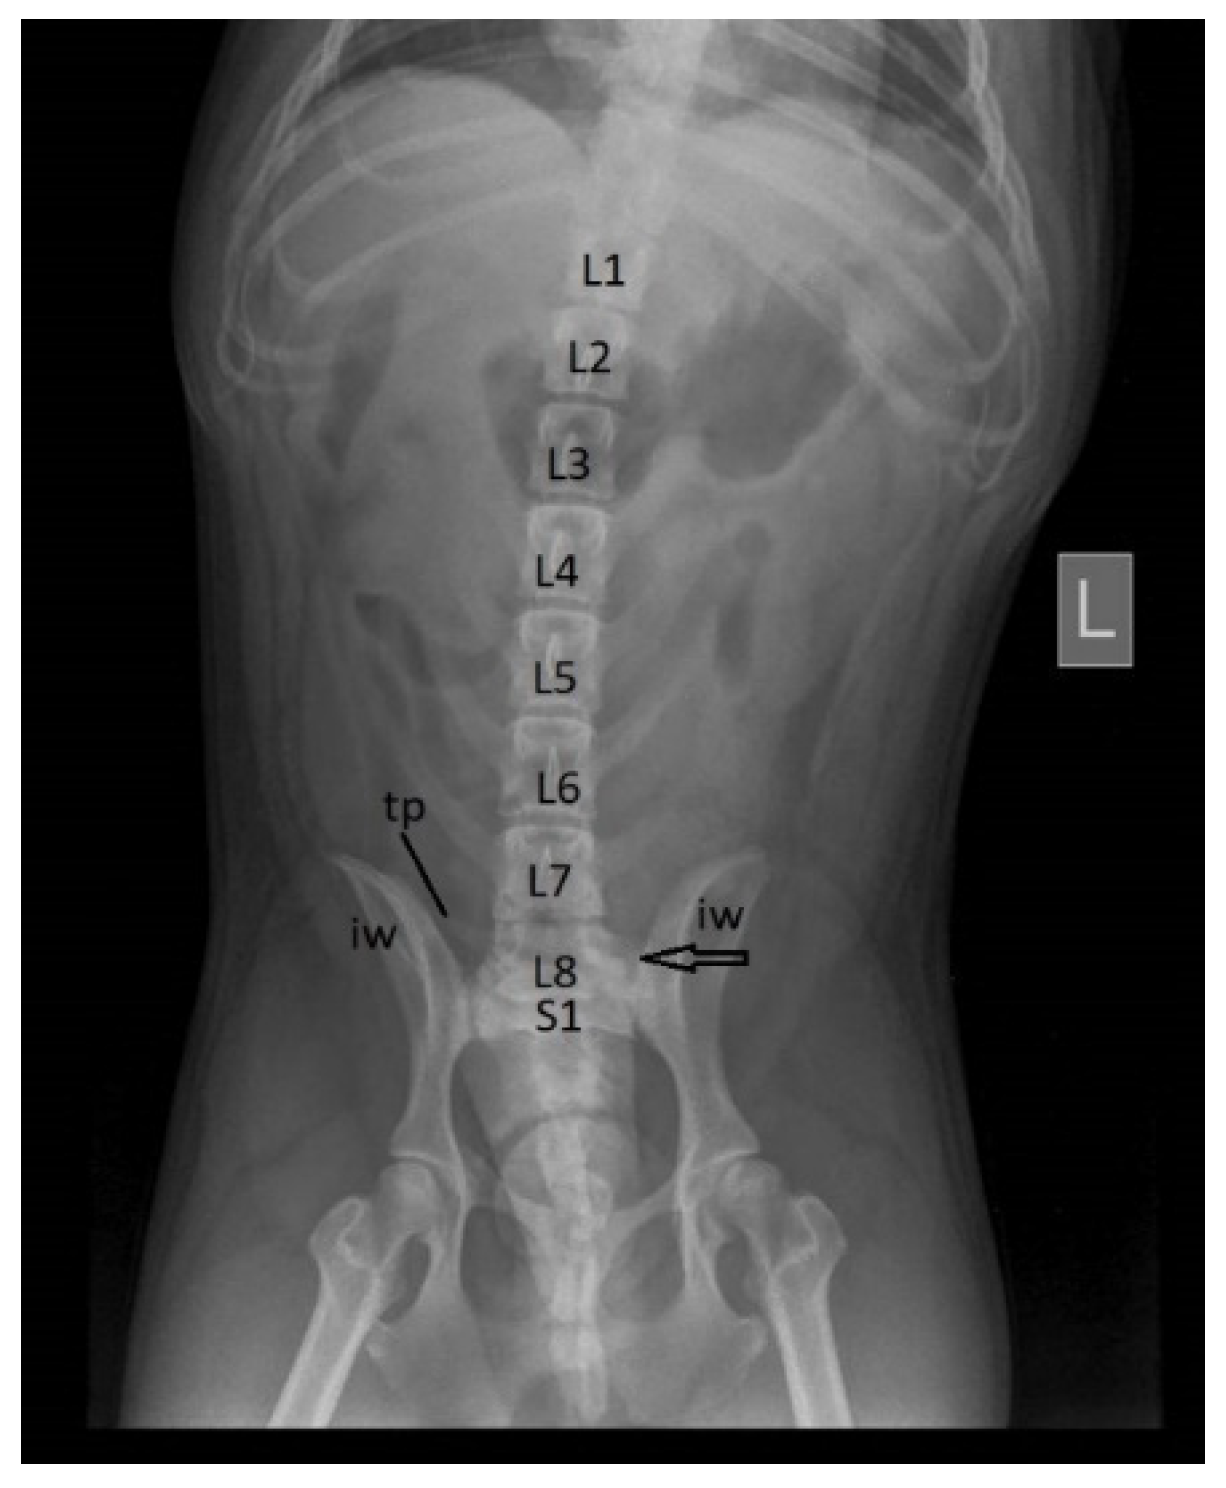

In cats, we found transitional vertebrae both in the lumbosacral region and sacrocaudal one. Two animals presented a large degree of sacralisation of the last lumbar vertebra. In a cat the transitional vertebra was associated with supernumerary vertebra, being counted 8 lumbar vertebrae, the last one being intense sacralised. The another cat presented sacralisation of L7. The sacralisation process was similar, being noticed that both transverse processes and the vertebral body were fused with those of the first sacral vertebra. It can be observed that the last lumbar vertebra (L7 or L8) is shorter, being almost entirely placed between the two iliac wings, and is no evident intervertebral disk between its body and the body of the first sacral vertebra. Also is visible that the transvers processes are shorter cranially and both are fused with the true sacral wings (the transverse processes of the first sacral vertebra) coming largely in contact with the iliac wings (Figure 13). There are present three sacral foramina on each lateral side of sacrum comparing with normal sacral bone in this species [25,26]. These aspects were observed at the x-ray exam.

Figure 13. Cat, female, 5 years – transitional lumbosacral vertebra-sacralization of L7 (last lumbar vertebra), ventro-dorsal view: L5 – the fifth lumbar vertebra; L6 – the sixth lumbar vertebra; S1 – the first sacral vertebra; tp – transverse processes of L7 – shortened and transformed in sacral wings; iw – iliac wing; vsf – ventral sacral foramina.

Preprints 91911 g013